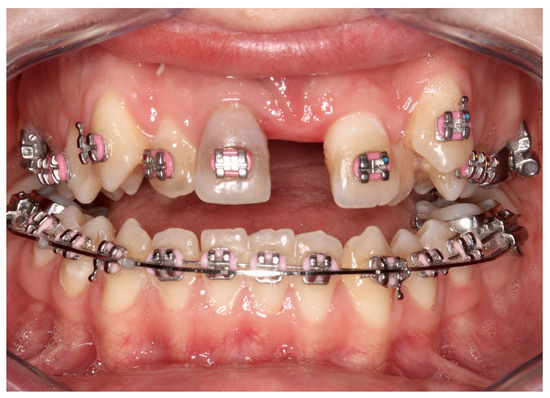

| No possibility of distraction—1 case | Maxillary incisor root resorption—2 cases |

| Palatal mucosal necrosis—2 cases | Bone loss/lack of adhesion in the distraction gap—5 cases |

| Perforation of the maxillary alveolar process caused by the distractor—1 case | Maxillary incisor necrosis—2 cases |

| Asymmetric distraction—5 cases | |